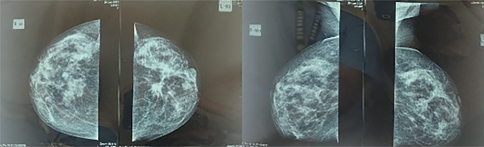

X-ray-based conventional mammography is a routine approach worldwide for breast screening (Figure 1). Several variations of x-ray-based imaging (XBI) technique is available, for example, digital breast tomosynthesis (DBT), and contrast-enhanced digital mammography (CESM), each with its own advantages and disadvantages (1, 3, 6).

Fig 1

Figure 1. Breast cancer mammography imaging: Left, craniocaudal view. Right, mediolateral oblique view. Image was provided by Division of Oncology, Department of Surgery, Faculty of Medicine, Universitas Sumatera Utara.